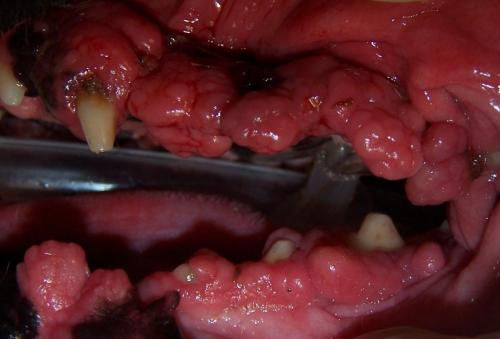

Severe gingival hyperplasia